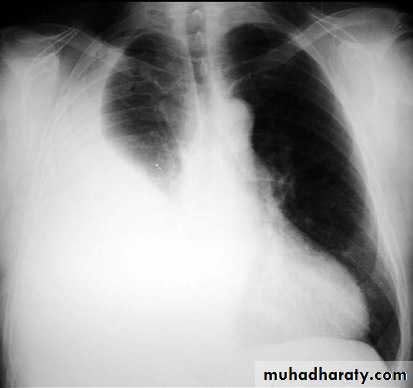

48.opasified hemi thorax Total collapse

Homogenus opacity of the right hemithorax with shifting of the trachea to the same side48.opasified hemi thorax Total consolidation

Homogenus opacity of the left hemithorax with central trachea

Total collapse

Homogenus opacity of the left hemithorax with shifting of the trachea to the same sidePleural effusion